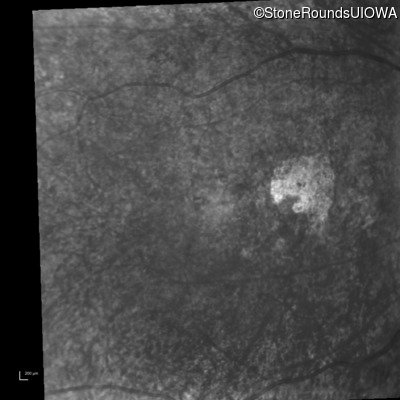

Infrared Fundus Photograph - Right - 20/1000 sc

Exemplar

Infrared Fundus Photograph - Left - 20/500 sc